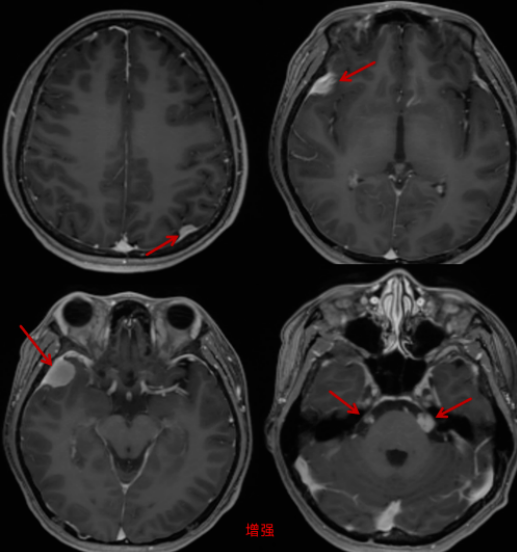

头颅MRI平扫+增强扫描检查,提示大脑镰旁、双侧顶部、双侧颞部及左侧小脑幕上部可见多发大小不等类圆形或梭形稍长T1等T2信号,增强扫描可见明显均匀强化,边界清楚,可见脑膜尾征;右侧脑室后角内可见类圆形稍长T1稍短T2信号,增强扫描可见较均匀强化;左侧内听道、双侧三叉神经可见多发结节状等T1等T2信号,增强扫描明显强化。